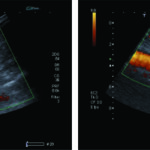

Los controles imagenológicos post tratamiento son de importancia, y es indispensable la caracterización morfológica del aneurisma y la endoprótesis. De esta manera, debemos medir el tamaño del aneurisma, la presencia de flujo dentro de la prótesis, la ausencia de flujo peri protésico, la presencia de flujo en arterias renales y la adecuada velocidad de flujo en las arterias ilíacas (Fig. 41, 42 y 43).

Las complicaciones luego de instaurado el tratamiento pueden ser el crecimiento del aneurisma, embolias, desgarros del tejido protésico, infección o migración del injerto, fractura de los ganchos, separación de una rama o la presencia de endofugas. Estas se clasifican en cinco tipos(24) (Tabla 6).

- Tipo I: hay presencia de flujo sanguíneo fuera del lumen protésico adyacente al sitio de anclaje. En Ia, proximal en la arteria y en Ib, distal en la arteria. Se produce por una mala fijación en el sitio de anclaje entre la prótesis y la pared arterial. Son más frecuentes en las endoprótesis torácicas, y se deben tratar en forma urgente (Fig. 44 y Fig. 45).

- Tipo II: son las más frecuentes. Se producen por flujo retrogrado desde una rama arterial excluida por la endoprótesis, y es común la afectación de la arteria mesentérica inferior y las arterias lumbares. La fase tardía de la angiotomografía identifica la presencia de contraste en la periferia del saco aneurismático que no contacta con la endoprotesis (Fig. 46).